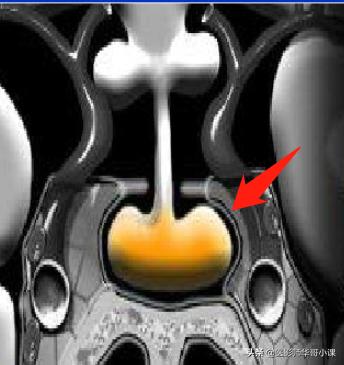

一旦发现孩子仍不长个,那就要去内分泌科检查,做一个激素水平检测,同样,建议必要时做一个“垂体磁共振平扫+动态增强扫描”。这样才能做出一个明确的判断,来选择药物干预的治疗方式,以免影响生长发育。